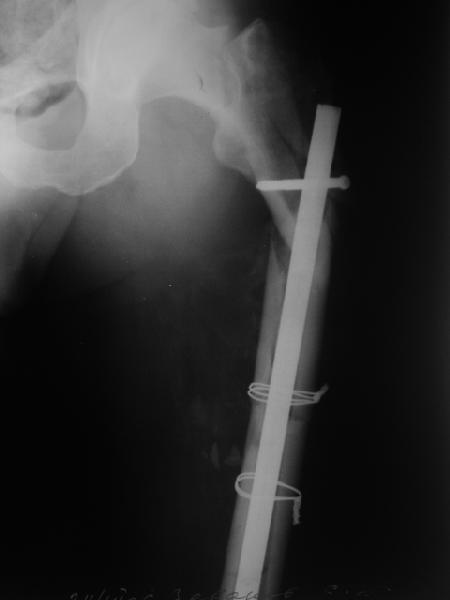

К нам поступил пациент 50+ лет. Оперирован чуть больше месяца назад в одном их городов области по поводу довольно банального поперечного диафизарного перелома бедра (снимок 1).

Выполнен удивительный остеосинтез стержнем S2 (Stryker) и проволокой (наверно, Smith&Nephew или Biomet, хотя, может, и попроще что-то). Пациенту затем с заверениями, что все сделано как надо, наложена была тазобедренная повязка из скотчкаста. Что имеется на сейчас - снимки 2 и 3.

Признаков инфекции нет (тьфу х 3). Подвижность явная.

Что делать дальше? Получилось сочетание проксимального и диафизарного переломов бедра, что только что обсуждали. Оптимально, наверно, пересинтезировать бедро длинной гаммой? Есть ли другие предложения? Спасибо!